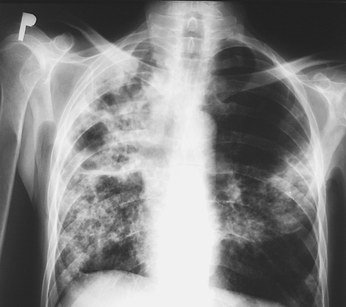

• RTG płuc - na zdjęciu można rozpoznać np. rozedmę płuc lub przewlekłe zapalenie oskrzeli.